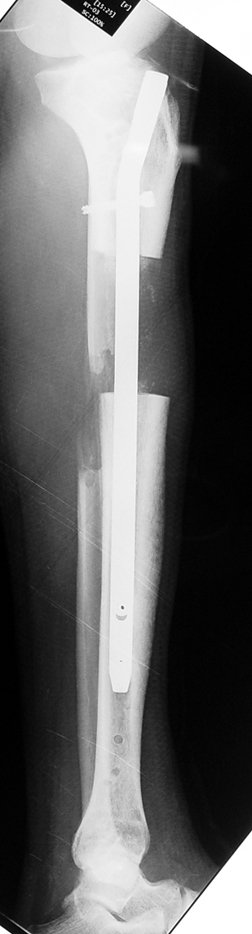

Installment of the intramedullary nail and osteotomy:

The patient lies is supine position at a traction table and legs are crossed with the uninvolved leg at the bottom. The medullary cavity is penetrated through piriform fossa using the standard method, and medulla is reamed 1.5 mm thicker than the nail to be used, over a guidewire. Proximal femur is reamed more, because the intramedullary nail is thicker proximally. The osteotomy site is planned at the X-Rays. It is important that at least 8 cm. of nail remains distal to the osteotomy site after the completion of the lengthening procedure. Percutaneous corticotomy is performed. The guide wire is advanced distally in order to measure the length of the nail. An intramedullary nail of apropriate length is placed. In the end, the nail is interlocked proximally, a suction drain is placed and the fist step of the operation is completed.

2. Step:

The application of the external fixator: Three Schanz screws are placed distally and three screws are placed proximally. At least 1 mm of distance shall remain between the screws and the nail.

In selected cases, we prefer to use a combination of a unilateral dynamic axial fixator and an interlocked intramedullary nail, in order to protect the length and alignment after the completion of the lengthening procedure. As a prerequisite for this technique, the narowest diameter of the medullary cavity shall be wider than 7 mm and the length of the nail segment distal to the osteotomy site shall be at least 8 cm. after the completion of the lengthening procedure.The intramedullary nail neutralizes shear and bending forces on femur during lengthening, shortens external fixation time, and protects newly formed bone against fractures. In our series, subtrochanteric osteotomy was performed in one case. No varus angulation occured despite the intramedullary nail.

Ilizarov stressed the significance of endosteal blood circulation for distraction osteogenesis. Although we placed the intramedullary nail after reaming the femur in all cases, the time for callus formation was not longer than expected. Thus we found that there is no slowing in the rate of new bone formation due to disruption of medullary blood flow. The rationale of this finding is revascularization that occurs following reaming of the medullary cavity, the fixation stability with the intramedullary nail and early functional weight bearing. The potential disadvantages of a combined use of external and internal fixation metods are increased blood loss, intramedullary infection, risk of fat embolism and excessive metal load.The most fearsome complication is a deep intramedullary infection (panosteomyelitis) triggered by pin tract infection.No such complication was encountered in our series. In order to avoid this complication, after the completion of lengthening the nail shaill be interlocked from the medial side, and contact of internal and external fixator pins shall be avoided.